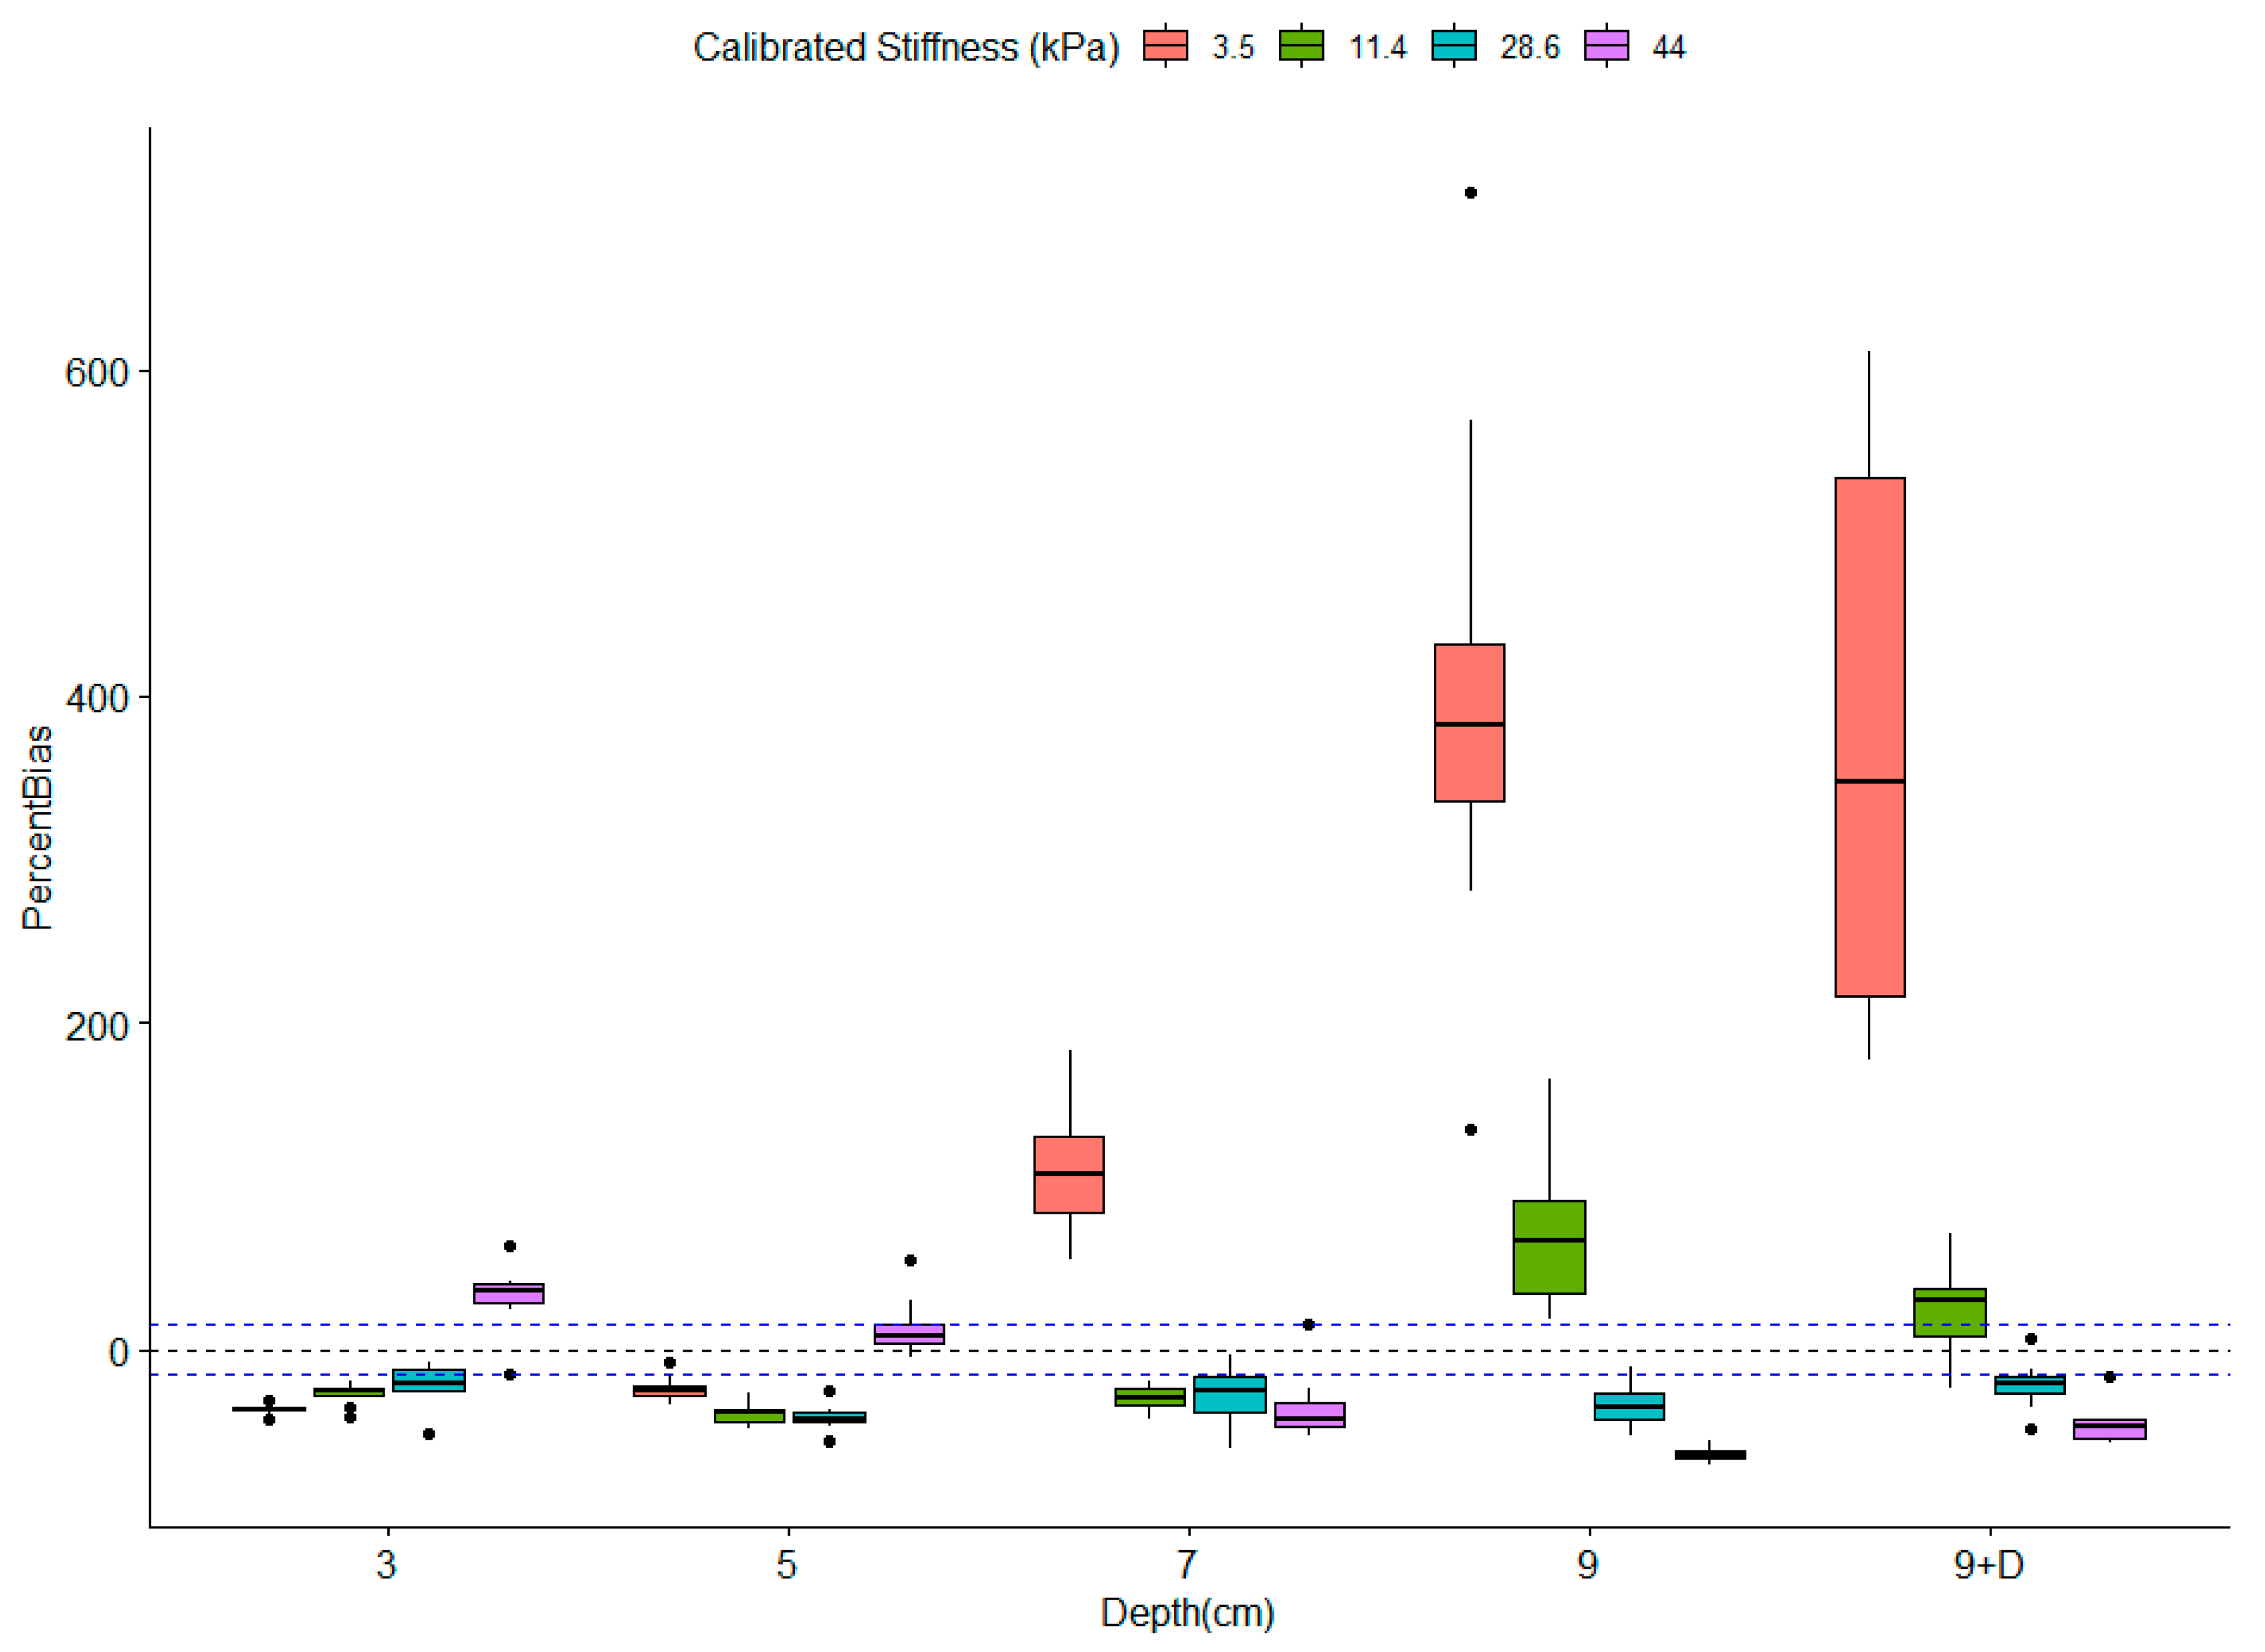

Impact of Depth and Acquisition Protocol on Hepatic Segment Stiffness Measurements

3.2. Influence of Depth on Measured Stiffness

3.3. Robustness of Texture Features in Healthy Livers